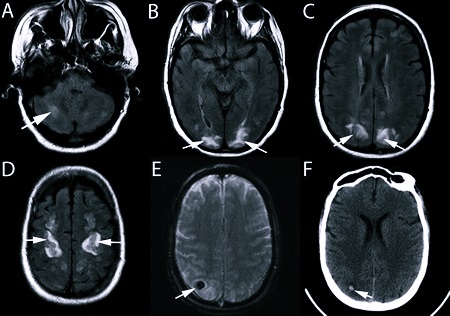

Для диагностики больному назначают множество процедур:

- ЭЭГ;

- ЭхоЭГ;

- КТ;

- МРТ;

- ЯМР;

- УЗДС;

- УЗДГ;

- РЭГ.